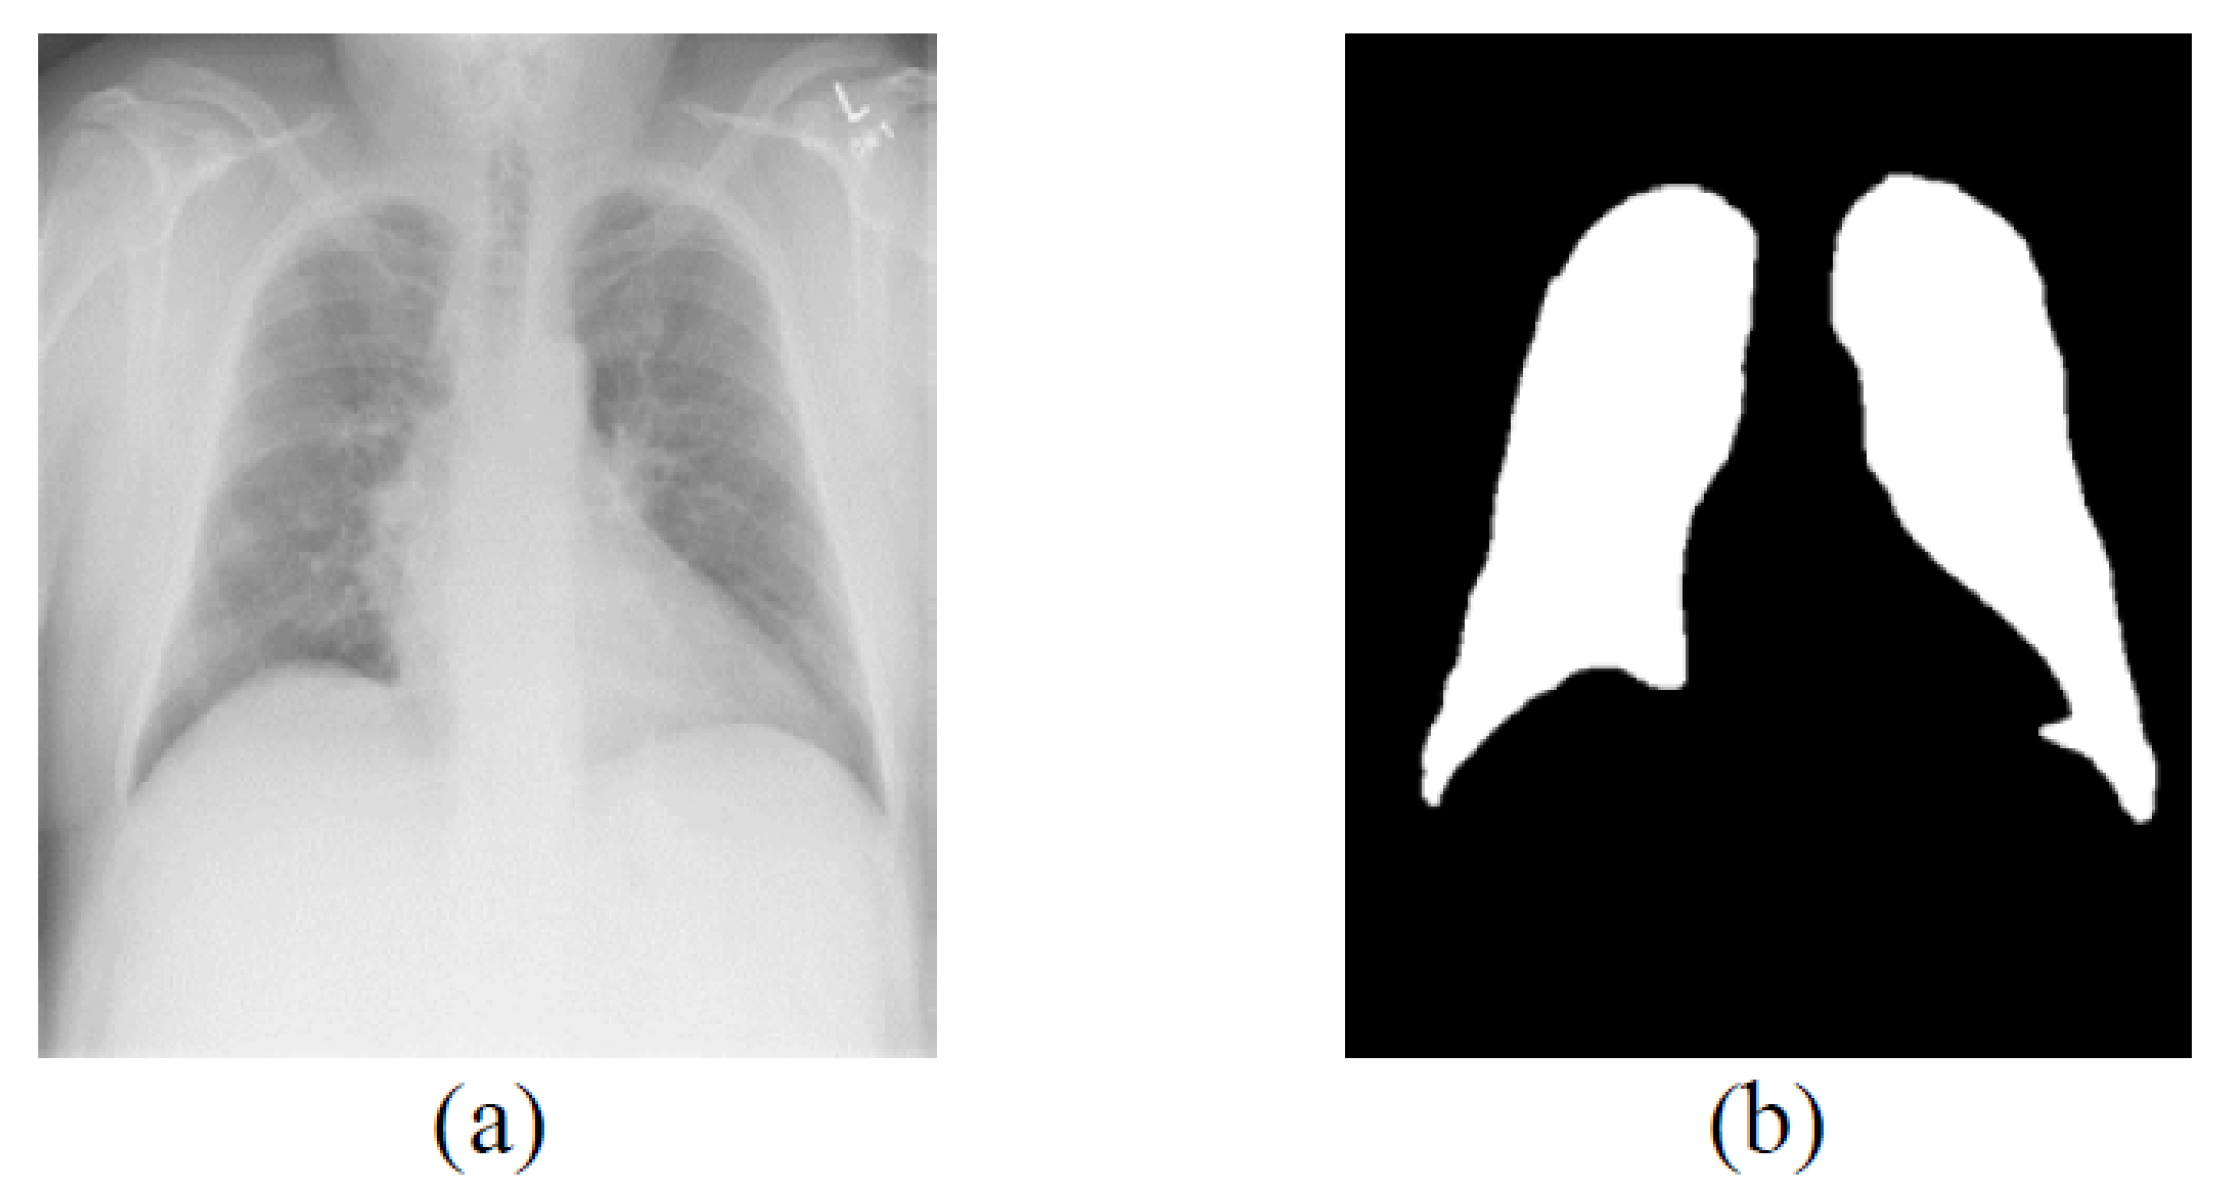

3.1. Datasets and Preprocessing

3.2. Overview of the Lung Field Segmentation